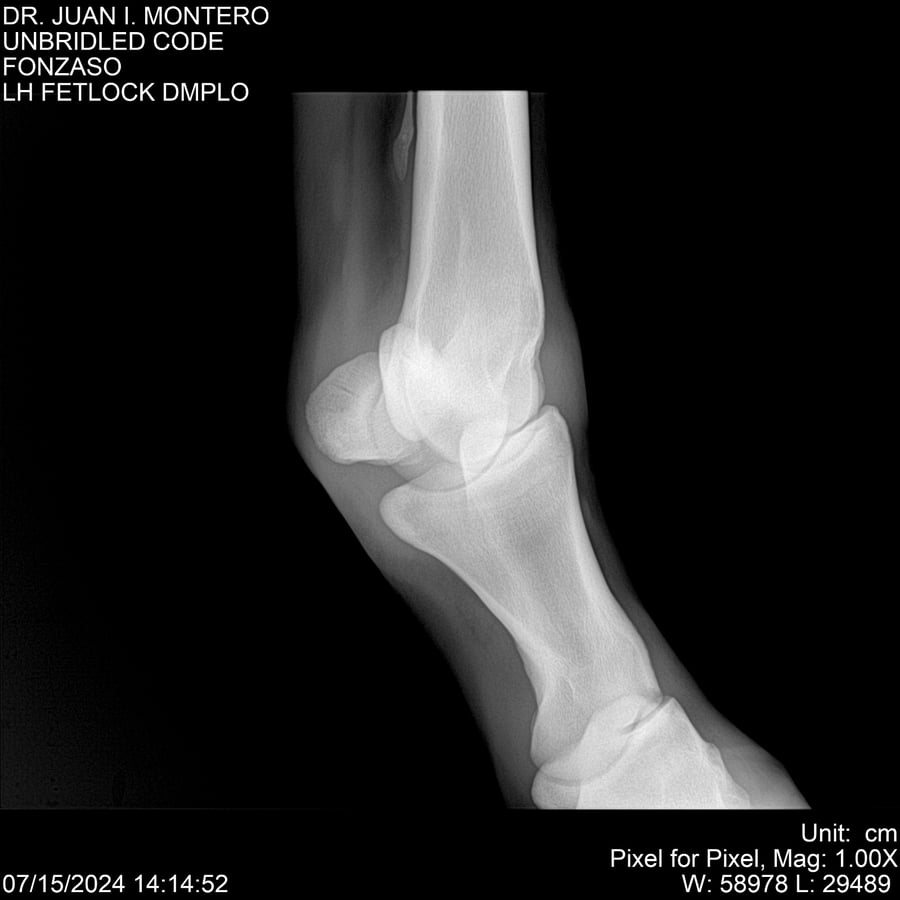

• Empresa: Abelenda N. R., Walter Hugo